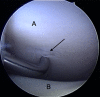

Intraosseous ganglia of the distal tibia are rare. We evaluated the feasibility of surgically treating these lesions with an arthroscopically assisted technique. Five patients with symptomatic distal tibial ganglia underwent surgical curettage and excision with this technique. All patients underwent débridement of the chondral lesion and hypertrophied synovial lining when present, probing of the portal to the ganglion, and subsequently thorough curettage with bone grafting performed through a cortical window made from a separate small incision. Biopsy confirmed the diagnosis in all patients. All patients had eventual relief of symptoms with good integration of bone graft at final followup. There were no recurrences at a minimum followup of 19 months (mean, 38.6 months; range, 19-69 months). Mean time for return to full function was 15.4 weeks (range, 8-17 weeks). There were no intraoperative or postoperative complications. The mean American Orthopaedic Foot and Ankle Society scores increased from 73 points (range, 67-77 points) preoperatively to 94 points (range, 90-100 points) postoperatively. Arthroscopically assisted surgical treatment of ganglia of the distal tibia in the appropriate patient is a reasonably simple technique that relieves symptoms and helps the patient to regain normal gait and full function with no recurrence (in our small series).